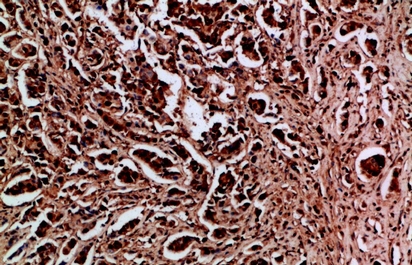

(Immunohistochemistry of paraffin-embedded Human breast cancer tissue using HDGF Polyclonal Antibody at dilution of 1:200.)